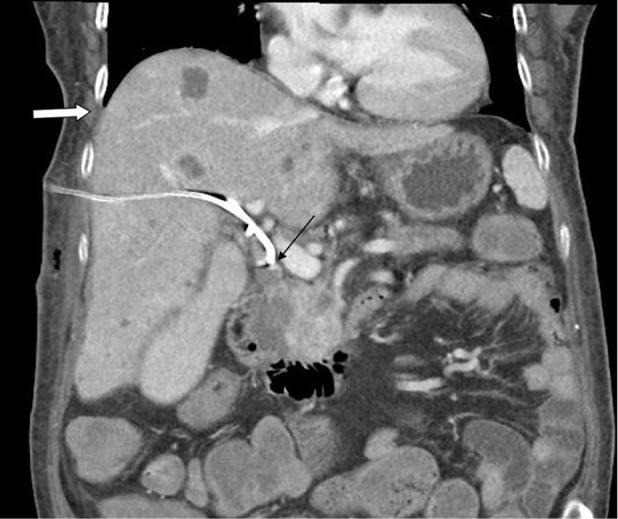

Biliopleural fistula (BF) and formation of biliopleural effusion is a rare complication following percutaneous transhepatic biliary drainage (PTBD). It occurs when the pleura is traversed by the catheter before entering the bile duct. Biliopleural fistula should be suspected when right side pleural effusion develops following the PTBD procedure. The diagnosis of biliopleural fistula is made when greenish pleural fluid with high concentration of bilirubin is aspirated. Here we present a case where a patient develops a biliopleural fistula following PTBD due to obstructive jaundice caused by neuroendocrine tumor of pancreas. Biliopleural fistula was disclosed after a scheduled catheter replacement procedure. Treatments of biliopleural fistula include thoracentesis with drainage tube installation into pleural space. In addition, a drainage tube was installed through percutaneous transhepatic gallbladder drainage (PTGBD) to reduce the bile induced pressure. Surgical repair of fistula was performed after the conservative treatment was unsuccessful. The patient expired 5 days after surgery due to respiratory failure.